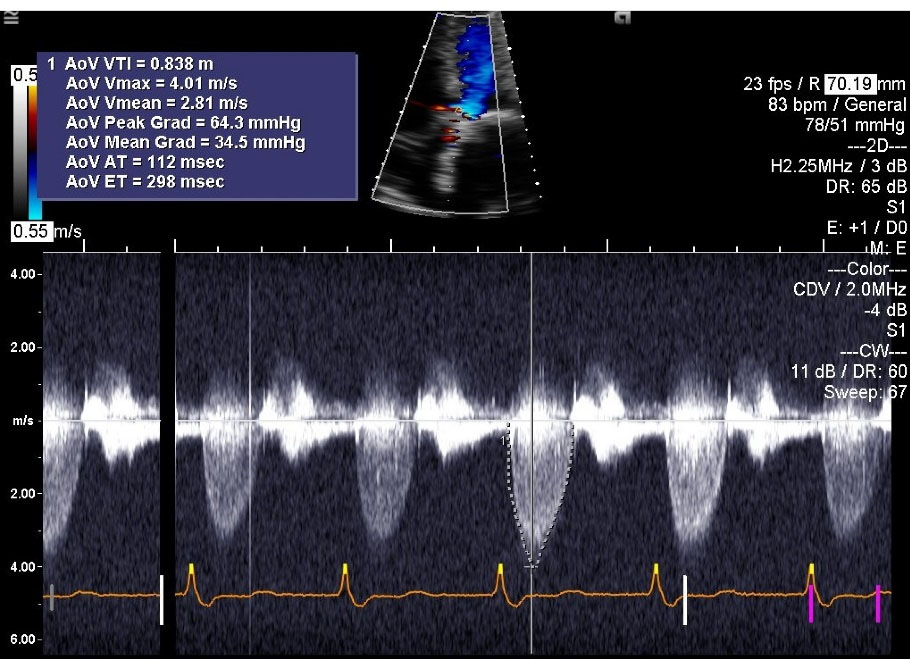

His acute decompensated heart failure was believed to be secondary to structural bio-prosthetic valve degeneration with associated critical stenosis and moderate regurgitation. Because of unstable hemodynamics, multiple comorbidities, high logistic Euro- score II of 67.0% and Society of Thoracic Surgery Risk (STS) score of 46%, the patient was deemed to be a poor surgical candidate for re-do surgical intervention. Therefore, he underwent immediate and successful TAVR with a ViV procedure with a 29 mm Medtronic Evout –R, using transfemoral approach with conscious sedation without complications. Follow up echocardiogram () one week post-procedure revealed prosthetic AV peak gradient of 64.3 mm Hg, mean gradient of 34.5 mm Hg, peak velocity of 4.01 m/s, and LVEF of 60%. The patient’s symptoms improved remarkably and he was discharged from the hospital after an extended stay of around 3 weeks. The patient had past medical history of CAD and was already on daily oral aspirin without any indication for concurrent dual antiplatelet therapy or any indication for anticoagulation. Another follow up echocardiogram at 5 months interval () revealed prosthetic AV peak gradient of 39.8 mm Hg, mean gradient of 23.0 mm Hg, and peak velocity of 3.15 m/s.

jcvtr-14-197-g002

Figure 2. 1 week post-TAVR echocardiogram; Color Doppler M-mode. Patient has 29mm Medtronic Evolut Pro bioprosthetic transcatheter aortic valve. AV peak gradient (AoV Peak Grad) is 64.3 mm Hg, AV mean gradient (AoV Mean Grad) is 34.5 mm Hg and peak velocity (AoV Vmax) is 4.01 m/s AoV, Aortic Valve